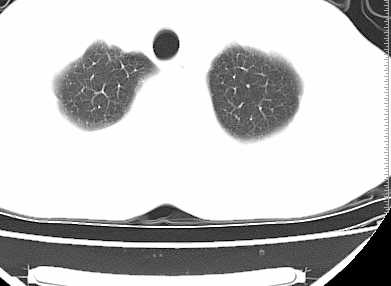

左侧中量胸腔积液伴左肺下叶肺膨胀不全、上肺外围多个小囊样腺泡样病灶。考虑化脓炎症。

患者刺激性干嗽,无咯血,伴心悸,低热,夜间无明显盗汗,消瘦明显,左侧中量胸腔积液伴左肺下叶肺膨胀不全、上肺外围多个小斑片病灶。考虑肺结核可能性大。

左肺舌叶及下叶见斑片状,大片状高密度影并相应处胸膜及心包不规则增厚,左肺下叶膨胀不全。右肺未见异常,双肺段以上支气管通畅。纵隔左移,其内未见明显肿大淋巴结。左侧胸腔积液。